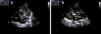

A male neonate was born at term. Obstetric ultrasound at 36 weeks showed two hyperechogenic masses, one located in the mid interventricular septum occupying the total thickness of the septum and the other attached to the anterior leaflet of the mitral valve. The baby was born by normal delivery, with a birth weight of 3280 g and an Apgar score of 10 at first minute and 10 at fifth minute. On physical examination, he had a grade III/VI systolic heart murmur best heard at the left sternal edge. An echocardiogram on day one revealed multiple masses with features of rhabdomyomas, located at the apex of the right ventricle, tricuspid and mitral valves, interventricular septum, left ventricular lateral wall and outflow tract. The left ventricular outflow tract mass (15 mm×9 mm) caused a peak gradient of 92 mmHg and a mean gradient of 49 mmHg (Figure 1a and b). The newborn underwent serial clinical and echocardiographic assessment. He remained asymptomatic and the masses underwent progressive reduction. At one month the left ventricular outflow tract mass measured 14 mm×8 mm and at latest follow-up at six months measured 12 mm×8 mm (Figure 2a and b). The peak left ventricle-aorta gradient had decreased to 29 mmHg, with a mean of 13 mmHg, at the last follow-up. A diagnosis of tuberous sclerosis was made by genetic testing, which confirmed a mutation in the TSC-2 gene.

(a) Six months, apical 5-chamber view: regression of the mass obstructing the left ventricular outflow tract, now measuring 12 mm×8 mm; (b) six months, parasternal long-axis view: clear regression of the mass. Ao: aorta; LA: left atrium; LV: left ventricle; RA: right atrium; RV: right ventricle.